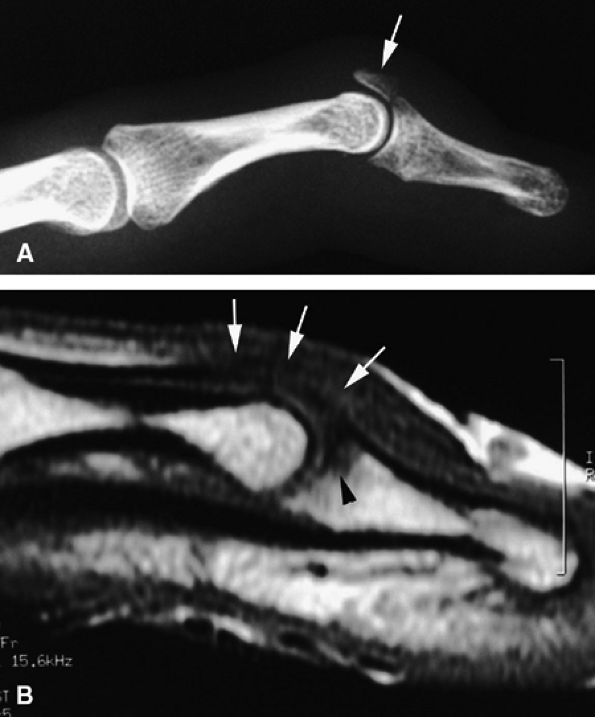

Type B mallet finger injury. High frequency ultrasonography, Xray and